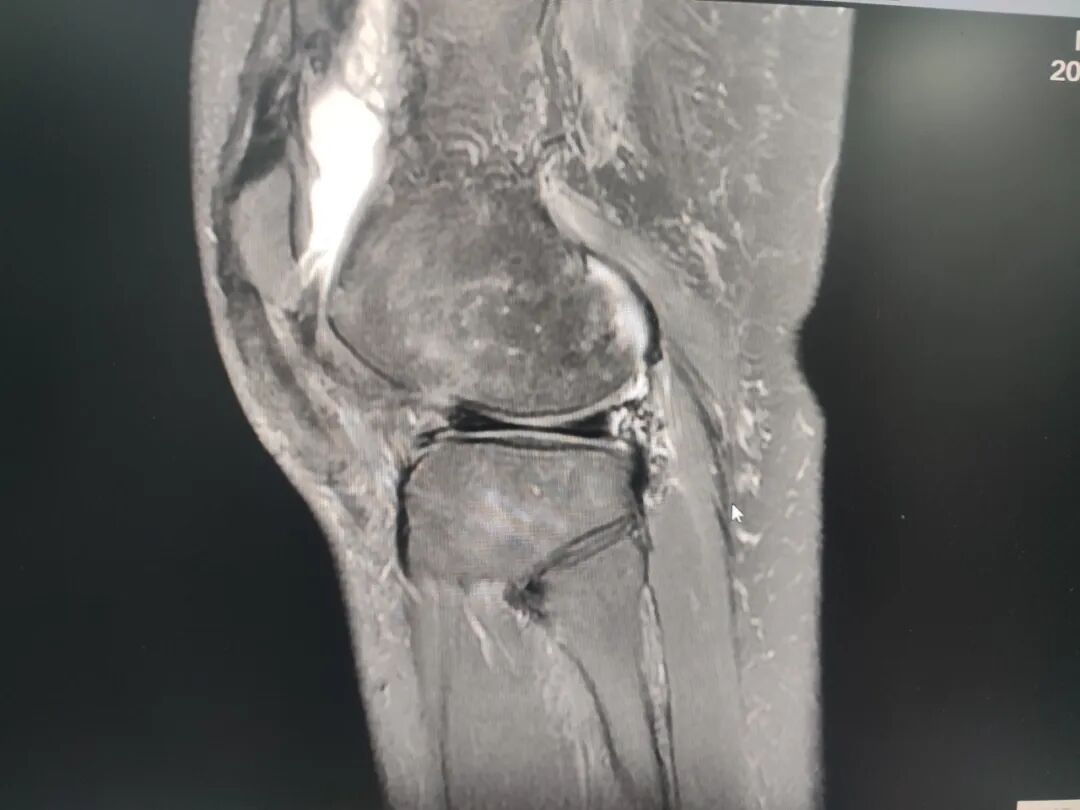

关节疼痛难忍?放疗精准“灭火”